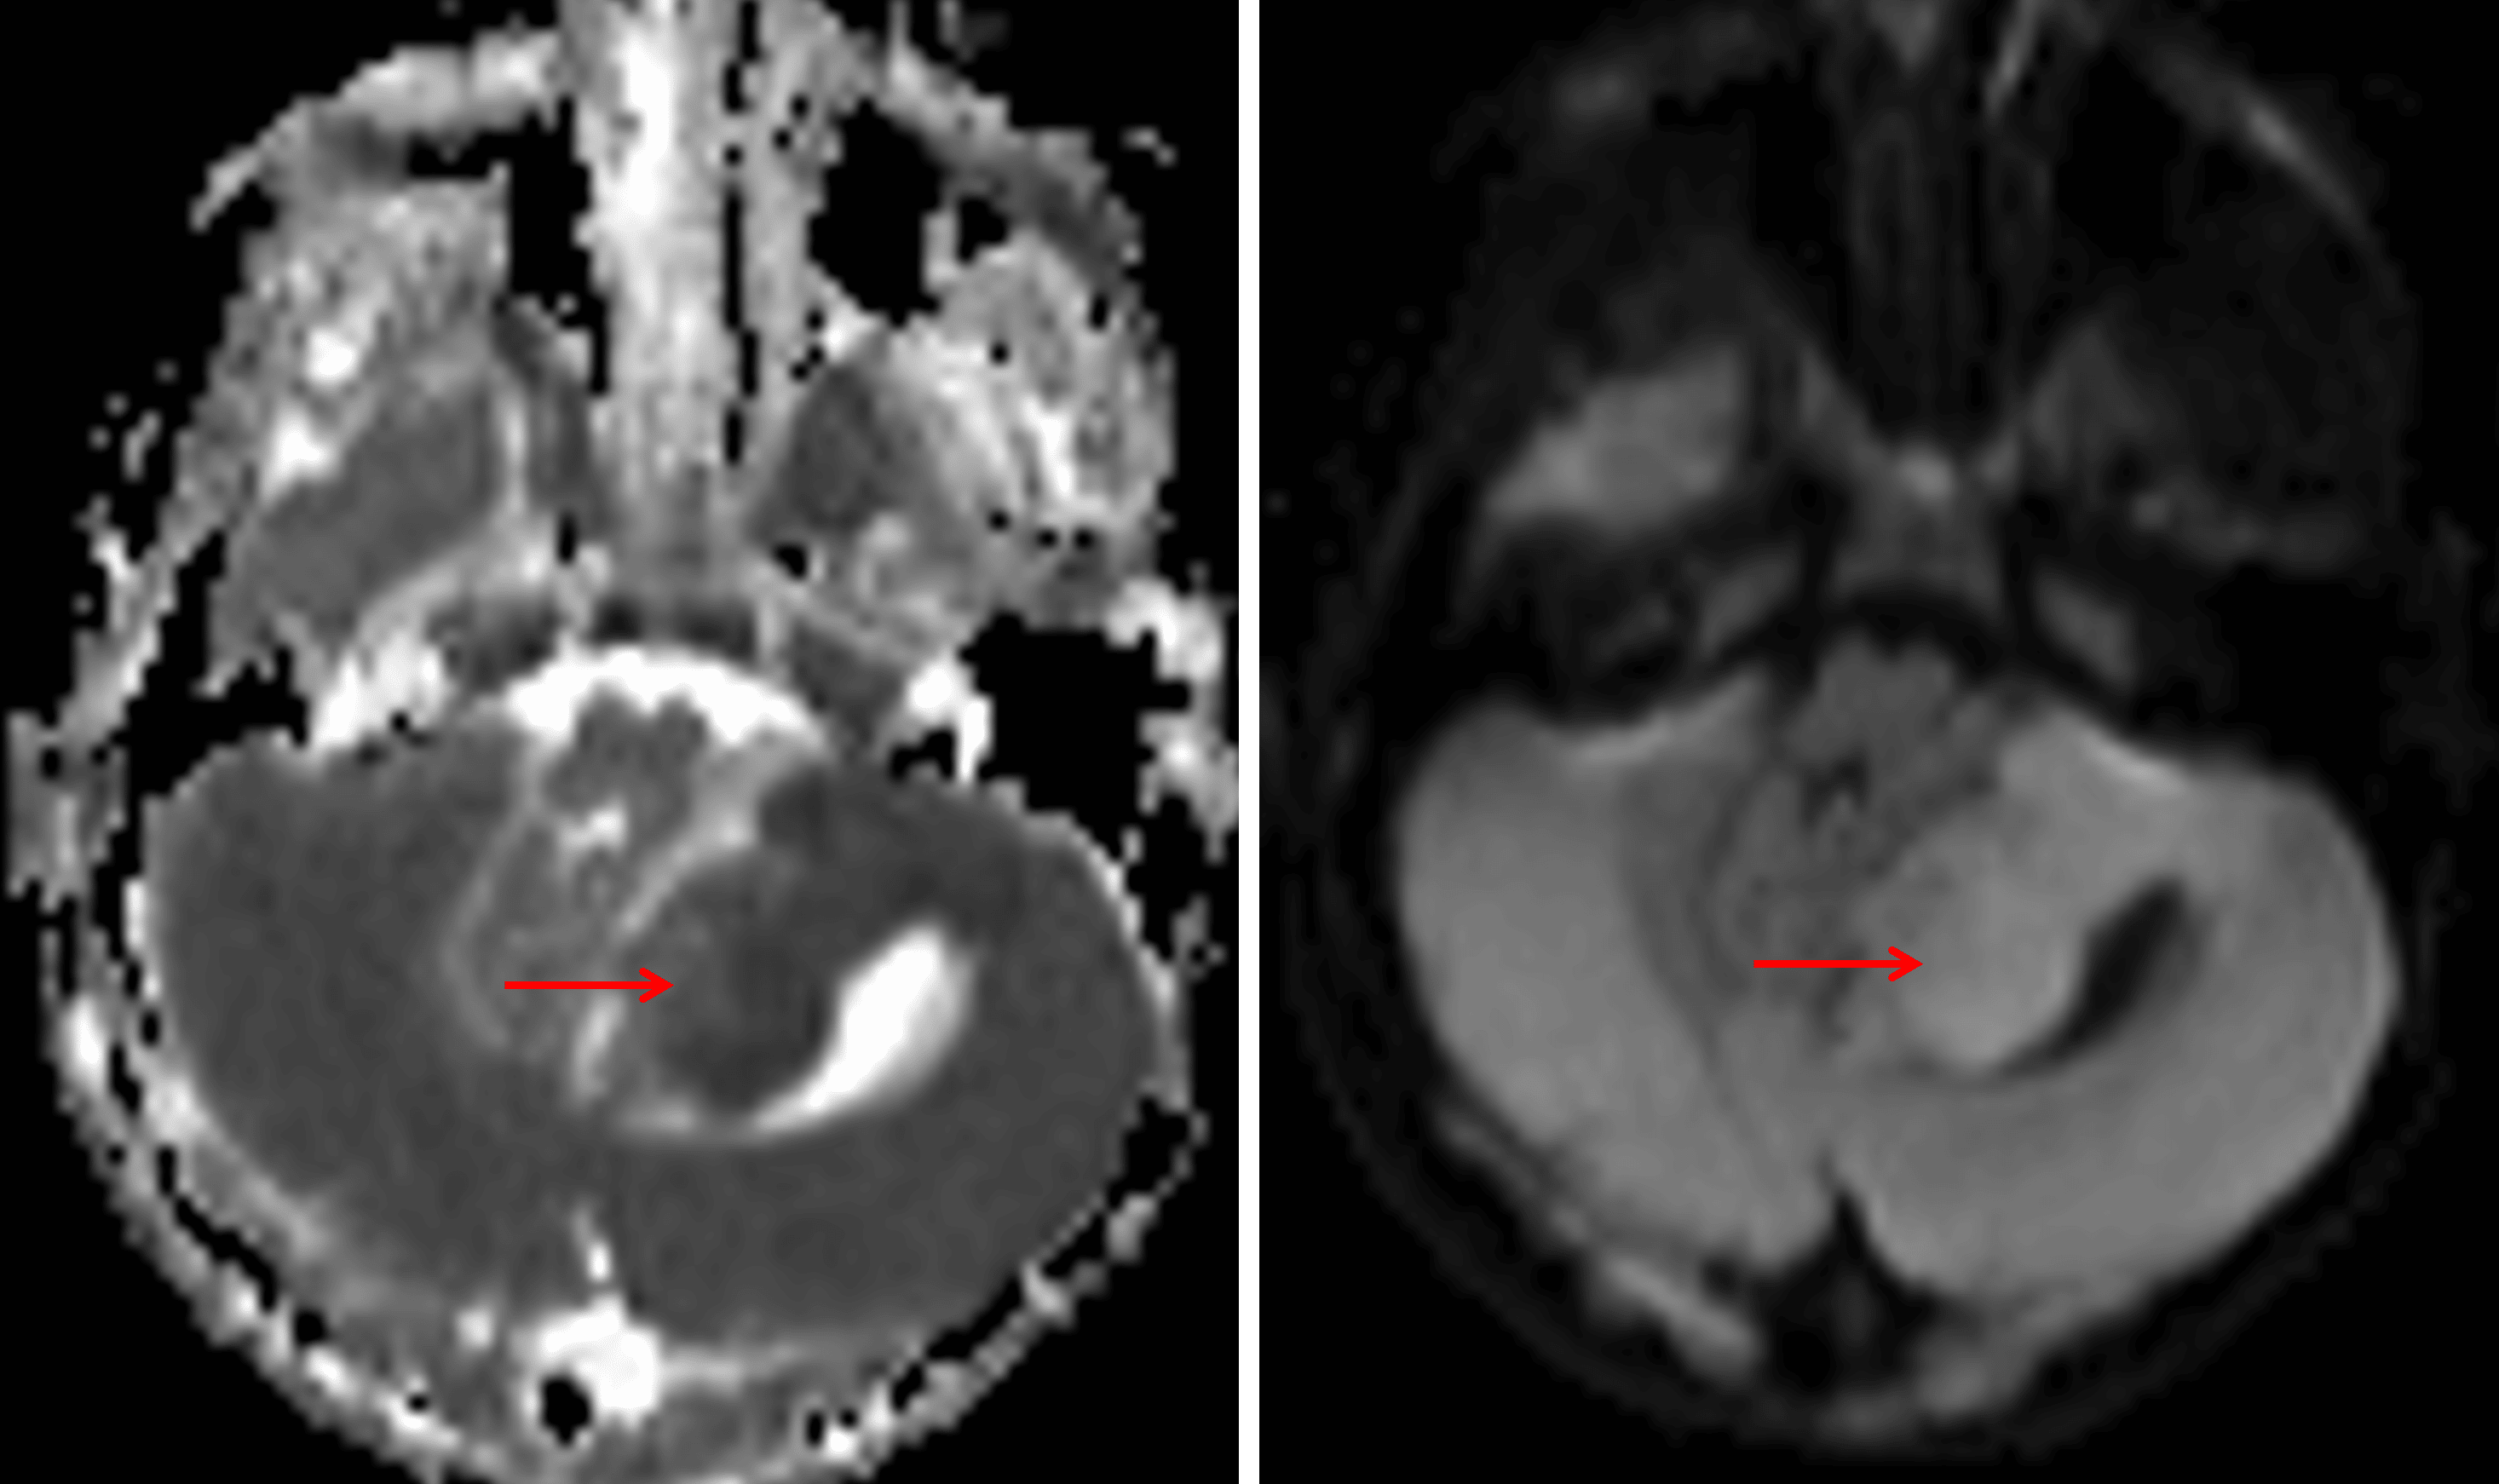

Mild corresponding restricted diffusion (red arrows).

• T1 hypointense, slightly T2 hyperintense mass centered in the inferior aspect of the left cerebellar hemisphere with diffuse enhancement and mild diffuse restricted diffusion